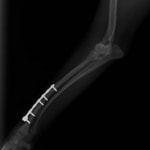

症例3:キルシュナーワイヤーのピンニングによる整復

ペルシャ猫 11ヶ月齢 雄

他院にて左大腿骨遠位の成長板骨折(salter-harrisⅠ型)が認められており、治療相談を目的として来院。当院にて、キルシュナーワイヤーを用いたピンニングにより骨折部位の整復を行いました。術後の経過は良好で、現在も経過観察中です。

術前レントゲン

術後レントゲン

機器

Arthrex社のターゲティングデバイスを用いてピンニングの位置を調整することで、確実な固定を行っています。当院ではこの手術器具以外にも、人の手術にも使用される様々な器具を導入し、手術精度を高め、また医療メーカーと新しい器具の開発、試作にも取り組んでおります。